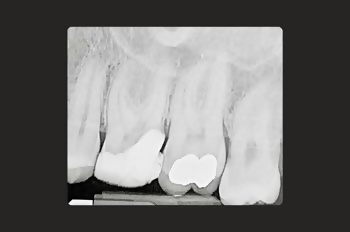

Root canal treatment is a restorative tooth-saving procedure that can avoid the need for an extraction.

Root canal treatments are a core aspect of endodontics, the dental speciality focused on treating infected tooth pulp and addressing complications from previous treatments.

Root canal treatment is needed when the tissues inside a tooth become damaged, infected, or inflamed due to deep decay, cracks, injury or repeated dental procedures on the same tooth.